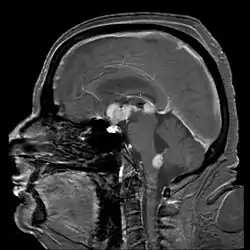

![]() تصوير بالرنين المغناطيسي للدماغ يُظهر لمفوما لاهودجكينية الخلية البائية الجهاز العصبي المركزي الأولية من السرج التركي ومنطقة تحت المهاد، ويستمر حتى السقف (مناطق بيضاء بشكل مكثف في الوسط). تصوير بالرنين المغناطيسي للدماغ يُظهر لمفوما لاهودجكينية الخلية البائية الجهاز العصبي المركزي الأولية من السرج التركي ومنطقة تحت المهاد، ويستمر حتى السقف (مناطق بيضاء بشكل مكثف في الوسط). | |